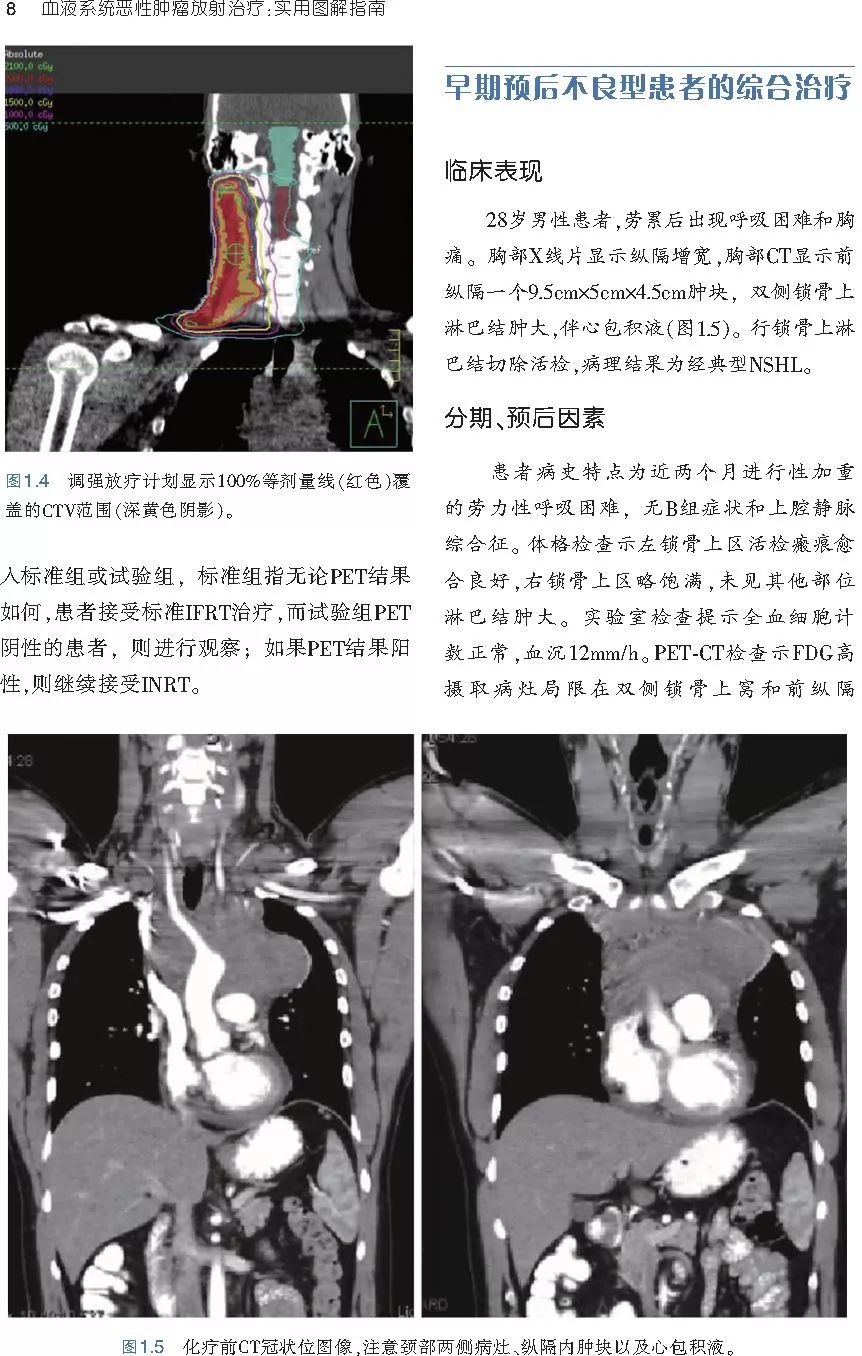

本书旨在帮助临床医生对常见血液系统恶性肿瘤疑难病例进行管理,包括霍奇金淋巴瘤、非霍奇金淋巴瘤和白血病患者,并通过多个病例进行阐述。案例讨论遵循标准格式,包括临床描述,其次是与诊断相关的病理描述和分期,然后详细讨论治疗选择。最后,确定治疗方案,并提供所使用的规划放疗技术/方式的图像。对放射肿瘤医生进行临床决策非常有帮助,对于血液病临床医生也有很好的指导作用。

近年来,放射治疗技术得到了迅速发展,调强放疗、图像引导放疗及其他新技术方法等,对恶性肿瘤治疗产生了巨大影响。现代放疗技术使精确定位、靶区勾画及给量成为可能,实现了肿瘤局控率和生活质量的双赢,对血液系统恶性肿瘤的临床治疗也产生了一定的影响。此书内容上不仅反映了血液系统恶性肿瘤综合治疗的进步,更是对其中放射治疗的新变化进行了系统、详细的阐述,这对当前血液系统恶性肿瘤放射治疗临床实践具有非常好的指导作用和参考价值。